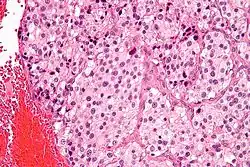

On microscopic inspection, the tumor cells are readily recognized. Individual tumor cells are polygonal to oval and are arranged in distinctive cell balls, called Zellballen.[9] These cell balls are separated by fibrovascular stroma and surrounded by sustentacular cells.

By light microscopy, the differential diagnosis includes related neuroendocrine tumors, such as carcinoid tumor, neuroendocrine carcinoma, and medullary carcinoma of the thyroid.

With immunohistochemistry, the chief cells located in the cell balls are positive for chromogranin, synaptophysin, neuron specific enolase, serotonin, neurofilament and Neural cell adhesion molecule; they are S-100 protein negative. The sustentacular cells are S-100 positive and focally positive for glial fibrillary acidic protein. By histochemistry, the paraganglioma cells are argyrophilic, periodic acid Schiff negative, mucicarmine negative, and argentaffin negative.

Micrograph of a carotid body tumor -